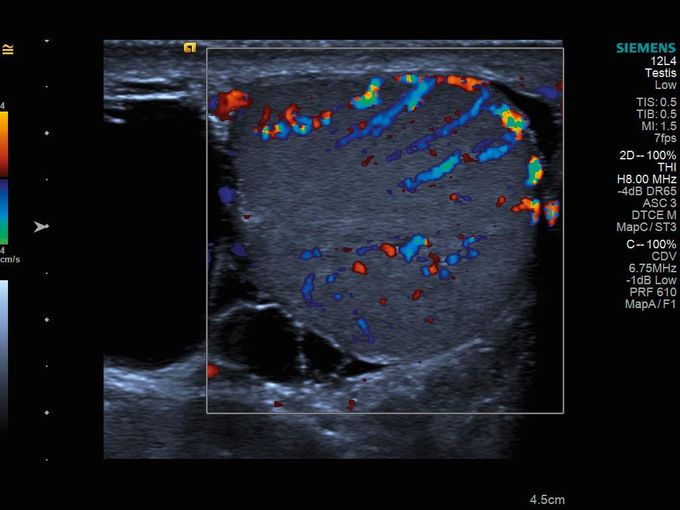

Кроме новой техники, можно заказать восстановленные медицинские системы: ультразвуковые сканеры, томографы, флюороскопы, ангиографы и хирургические установки С-дуга.